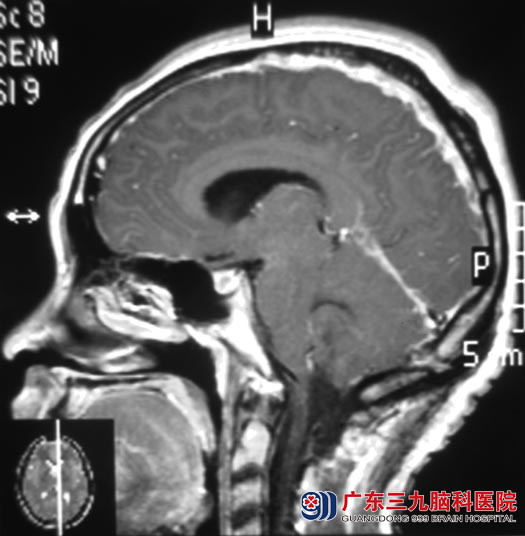

之后,小林逐渐出现头晕症状,才想起去医院检查,头颅CT检查提示左侧小脑半球占位。http://www.999brain.com/

广东三九脑科医院综合神经外五科 鲁明主任告诉小林:小脑参与躯体平衡以及随意运动的协调,小林不能走直线于小脑病变有关。头颅MR检查是左侧小脑半球囊实性占位性病变。

12月12日,由鲁明主任主刀,在全麻下行左侧小脑半球血管母细胞瘤切除术,术中探查见近窦汇小脑蚓部、左小脑半球有部分肿瘤裸露,肿瘤呈囊实性,打开囊壁,吸除淡黄色囊液,见灰褐色瘤结节位于左侧小脑,质软、血管丰富并杂乱生长、无包膜,边界较清,显微镜下分块全切除肿瘤。术后,小林自诉头晕症状较前好转,走路也没有再偏斜那么厉害了。术后病理结果为:血管母细胞瘤(相当于WHO I 级)。